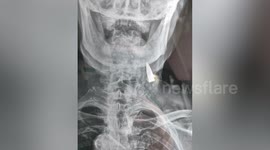

A police constable in Firozabad, Uttar Pradesh in India said he escaped certain death when a bullet passed through his bulletproof vest but was stopped by his wallet.

Vijender Kumar, 24, said he was now celebrating his “second life” after he was shot in the chest as protests against a controversial citizenship law descended into violent clashes on Friday.